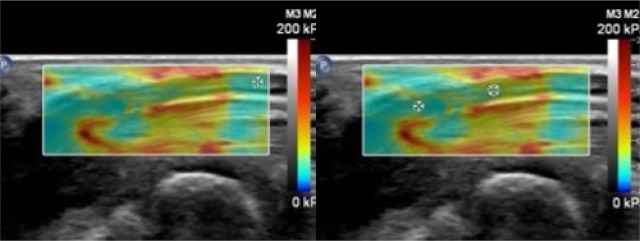

La SWE se realizó en plano longitudinal, esperando la estabilización del nervio en pantalla antes de congelar la imagen y analizar el elastograma: un mapa codificado por colores que representa la rigidez del tejido:

- El rojo indica zonas de mayor rigidez,

- El azul representa tejidos blandos,

- Y los tonos verde-amarillo corresponden a rigidez intermedia.

Elastrografía en paciente sano